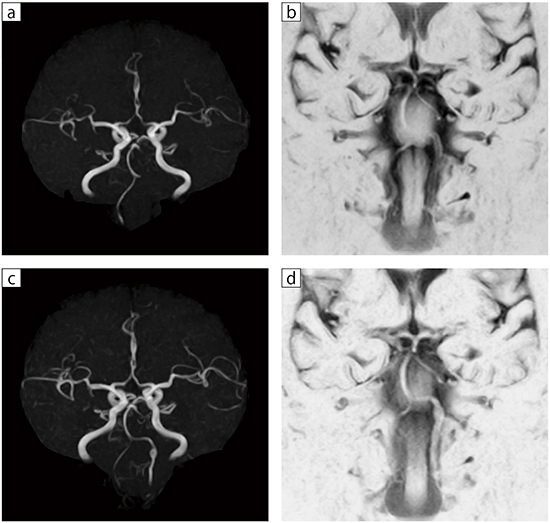

■症例2:左椎骨動脈解離

72歳,女性。左後頭部痛とワーレンベルグ様の一過性の虚血症状あり。MRAでは左椎骨動脈は描出されなかったが(a),BPASでは描出された(b)。以上より,左椎骨動脈解離と診断した。保存的治療施行約1か月半後のMRAでは,左椎骨動脈の再開通と解離性脳動脈瘤を認めた(c)。BPASでも同様の脳動脈瘤を認めた(d)。

a,c:MRA MIP,TR/TE=33/6.5,スライス厚:1.3mm,

FOV:180mm,FA:30°

b,d:BPAS,TR/TE/TI=4450/300/1200,スライス厚:2.0mm,

FOV:140mm,FA:90°